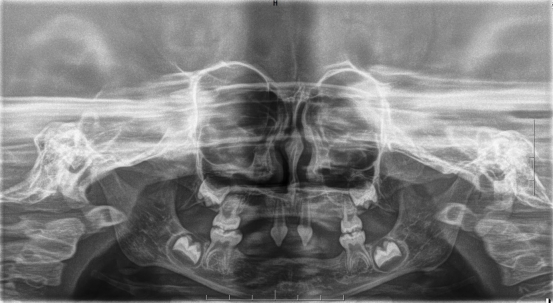

近年来,williamhill官网附属口腔医院(后文简称贵医口腔)在临床诊疗方面每年均有多个技术创新或突破。期间,副经理、口腔修复种植科主任医师王永曾带领团队完成多名外胚层发育不全患儿的可摘局部义齿及全口义齿修复,222日,更是为一位4岁患儿完成了罕见外胚层发育不全可摘局部义齿修复该患儿为目前口腔医院完成修复治疗年龄最小的患者

患者4岁,乳牙未正常萌出,上颌仅4下颌仅2颗乳牙,不能正常咀嚼,于2022年底在外地就诊多次无法修复,专程到口腔医院就诊。在后疫情时期,患者经王永门诊诊治后商讨出诊疗方案医院细心安排,于222由王永带领谭雯珈、姜炜鹏等医师,使用修复、正畸、修复工艺等多项技术,顺利完成了大面积乳牙缺失修复患儿现场进食效果良好,家长及患儿十分满意。

因其口腔表征为先天缺牙甚至无牙颌,且缺牙患儿口内余留牙往往表现为锥形牙、釉质发育不良、牙槽嵴发育不良等,可严重影响患儿的咀嚼功能及面部软硬组织生长发育。